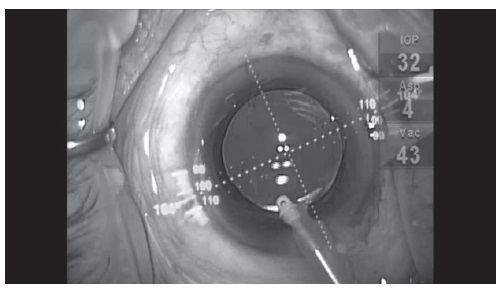

トーリック眼内レンズは、角膜乱視のゆがみを打ち消すような特殊なゆがみをつけたレンズです。これによって乱視の強い人でも、裸眼でよい視力が得られるようになります(図表3)。

ただし、乱視のゆがみの量やゆがみの角度などが正しくあっていないと、期待したような効果は得られません(図表4)。手術するときは、乱視矯正技術の高い医療機関で施術を受けることをお勧めします。